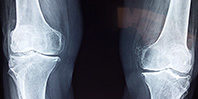

Стандартно лечение рака костей предполагает курс химиотерапии и оперативное вмешательство с удалением пораженной ткани. Обычно вместо удаленного участка кости ставится металлический, керамический или полимерный имплантат. Но такие имплантаты отличаются по структуре от костной ткани.

В частности, титановые имплантаты принимают на себя слишком много нагрузки, предназначенной для кости, и последняя начинает истончаться, на стыке с имплантатом — ломаться. Керамические изделия отличаются большей хрупкостью (есть ограничения по используемому объему и требуется постоянная плотная фиксация). Сверхвысокомолекулярный полиэтилен является биосовместимым материалом, который удобен в работе и использовании.

. Известно: имплантат пересаживали догу, у которого было удалено около 11 сантиметров кости. На титановую трубку, изготовленную методом 3D-печати, ученые нарастили слой сплошного сверхвысокомолекулярного полиэтилена, а внутреннюю часть выполнили из пористого сверхвысокомолекулярного полиэтилена, идентичного структуре губчатой кости. Во время операции часть покрытия срезали, чтобы подогнать имплантат к кости. Если срастание полимера с костной тканью пройдет успешно, фиксирующие пластины будут удалены.